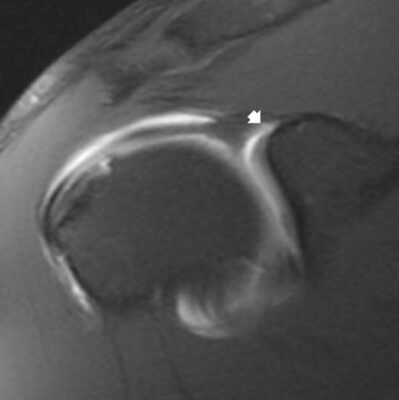

- Cộng hưởng từ: Với bệnh nhân nghi ngờ khả năng bị tổn thương sụn viền cao trên lâm sàng, cần chụp MRI để xác định. Một số trường hợp MRI có thể không xác định được rách SLAP, do đó có thể sử dụng chụp khớp cộng hưởng từ (MRA), có độ nhạy tốt hơn. MRI có thể có kết quả dương tính giả do nhầm với ngách sụn viền trên, làm cho chẩn đoán khó khăn. Một ưu điểm khác của MRI là để phát hiện những thay đổi bệnh lý trong khớp và ngoài khớp trong các mô mềm khác.

- Với rách sụn viền, MRA có độ nhạy 82 – 95,6%, độ đặc hiệu 69 – 98% và độ chính xác 74 -90 %.

- MRI: Những bệnh nhân bị tổn thương Bankart phần mềm, phim X quang có thể không phát hiện được gì. MRI sẽ là nghiên cứu hình ảnh tiếp theo được thực hiện. Trong bối cảnh cấp tính, MRI không thuốc là phù hợp vì máu tụ do trật khớp hỗ trợ nhìn sụn viền. Trong trường hợp mạn tính, chụp khớp cộng hưởng từ (MRA) có thể cải thiện hình ảnh sụn viền.